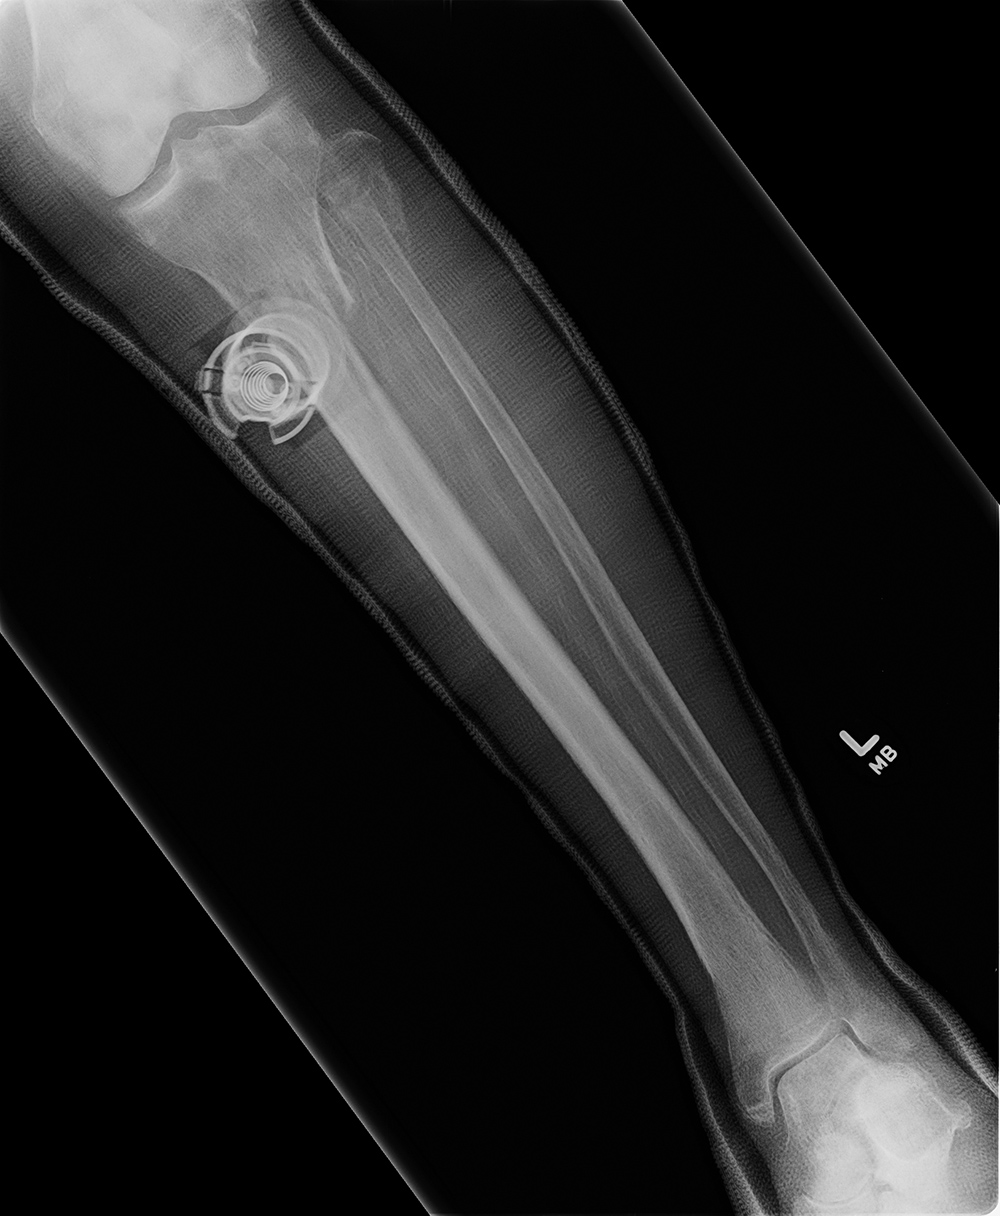

43 year-old man with comminuted right tibia and fibula fractures as well as extensive bone loss and soft tissue injury. A tibial intramedullary nail with proximal and distal locking screws is present as well as multiple rounded bony allografts. There are also large skin staples.